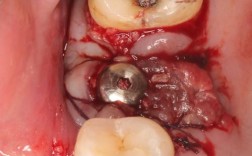

- 手术创伤刺激:种植过程中,术区需切开牙龈、剥离骨膜、制备种植窝,甚至可能进行骨增量(如植骨),这些操作会损伤局部小血管和淋巴管,导致组织液渗出,引发肿胀。

- 感染因素:若术中无菌操作不严格、术后口腔卫生维护不当或自身免疫力低下,可能导致细菌侵入,引发局部感染,加重肿胀。

- 术中微创操作:选择经验丰富的医生,采用微创种植技术(如数字化导板种植),减少组织损伤和手术时间。